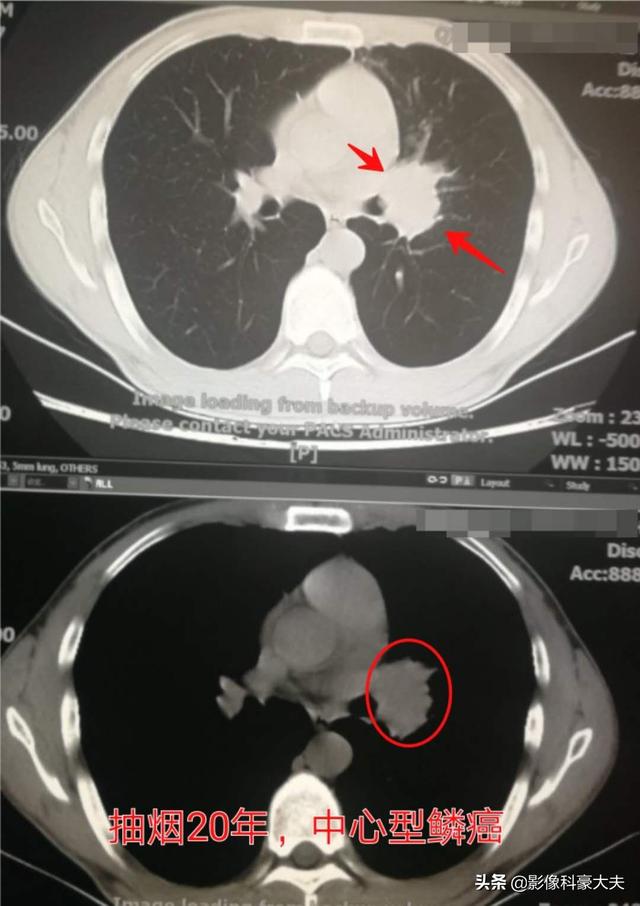

この男性患者は30歳そこそこで、20年間喫煙しており、2年前に咳が再発し、時々痰に血が混じることから中心性扁平上皮肺癌と診断された。それ以来受診しておらず、生きているかどうかもわからない。10代でタバコを覚えなければ、こんなに若くして肺癌になることはなかっただろう。